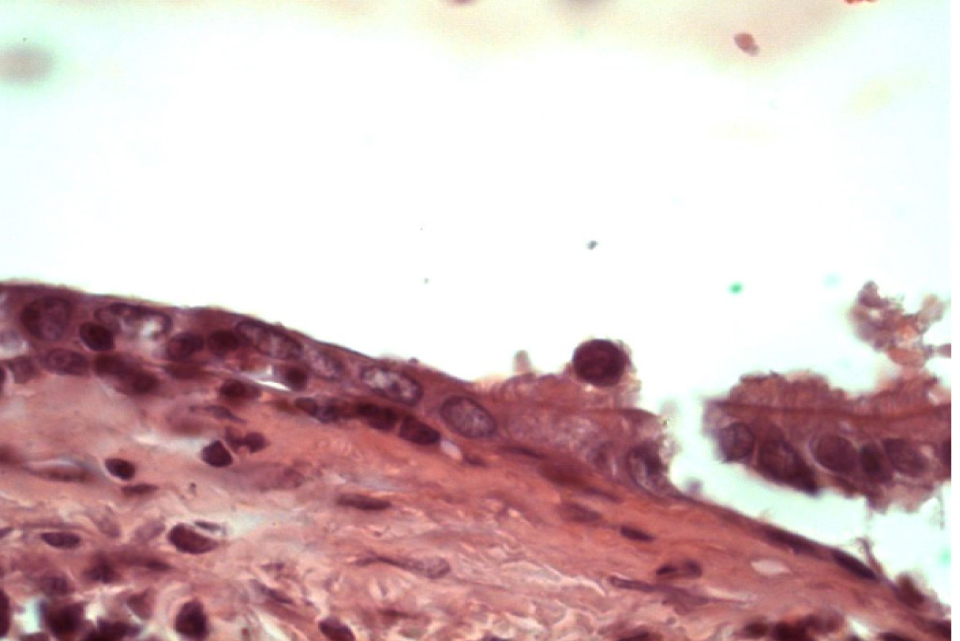

Многорядный мерцательный эпителий бронхов подвергается различным дегенеративным изменениям. Высота эпителиального пласта варьирует. Встречаются участки как плоского, так и кубического эпителия, мерцательные клетки которого содержат немногочисленные реснички (рис. 5).

Рис. 5. Участок различного по высоте эпителия бронха. Окраска гематоксилином и эозином. Ок. 10. Об. 100. Иммерсия

Появляются зоны безреснитчатого эпителия, что связано с токсическим действием фталата свинца, а также травмированием ресничек его частицами (рис. 6).

Рис. 6. Участок эпителия бронха, лишенного ресничек. Окраска гематоксилином и эозином. Ок. 10. Об. 100. Иммерсия

Рис. 8. Образование однослойного плоского эпителия, замещающего участки повреждения. Окраска гематоксилином и эозином. Ок. 10. Об. 100. Иммерсия